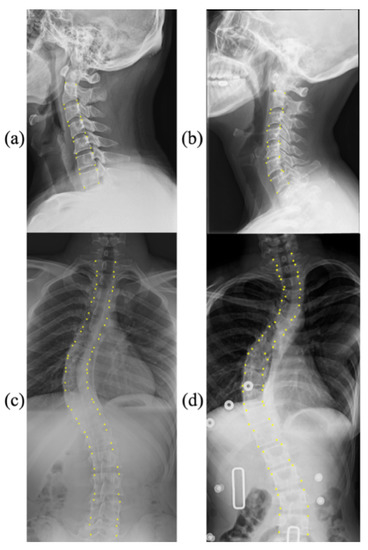

3.5. Visualization

Figure 3 shows the Cobb angle estimation results for six examples. We provide the corresponding ground-truth labels as a comparison. In cases 1–5, the difference between the ground truth and our prediction was much less than 2 degrees, which shows the accuracy of landmark detection and Cobb angle estimation. We also show a failure case (Case 6) with a difference of more than 4 degrees. The statistical comparison is visualized in Figure 4 and Figure 5.

In addition, it is necessary to discuss the influence of illumination on the experimental results to ensure the reliability of computer-aided diagnosis results. The impact of lighting problems on computer-vision tasks is expounded in [30]. In this work, the mean absolute error was 3.64° for the AASCE2019 dataset and 1.79° for the CS799 dataset. From analyzing the lighting situation in the dataset, one reason for the smaller average error on the CS799 dataset may be because the image lighting situation in CS799 is more stable than that in AASCE2019. Most of the images in AASCE2019 are shown in Figure 1c,d, with significant changes in illumination. While the CS799 images are shown in Figure 3, the changes in illumination are not obvious. For these two different tasks, the goal is the same. Their goal is to find the optimal algorithm to reduce the error of Cobb angle estimation. For AASCE2019, another requirement is that the algorithm should be robust against noise and lighting changes; this means that the AASCE2019 dataset has higher requirements for the algorithm.

We demonstrated the effectiveness of each module through ablation experiments on the CS799 dataset. At the same time, the method was applied to the AASCE2019 dataset, which proved that the method is still robust to illumination and noise changes. However, there are also some limitations in our work. First, our method was only implemented on frontal images of the public database, with no involvement in the complex conditions of clinical practice. In addition, sagittal alignment also plays an increasingly important part in clinical outcomes, and researchers should pay more attention to it. Although our experiments were limited to frontal spine images, our method can overcome huge variations and high ambiguities of the public dataset. The performance of our model implies its robust adaptability to the high-definition in-house images, which will be performed in future research. Second, our automatic method may occasionally yield an incorrect result (see Case 5 and Case 6 in Figure 3). We will continue to optimize the network model to narrow the confidence interval. Third, our methods have not yet provided classification results for cervical spondylosis and scoliosis severity. A professional medical analysis and diagnosis results must be combined with professional medical field knowledge, which is also a shortcoming of our method.

Figure 3. Six samples of landmark detection and Cobb angle estimation using our model and the ground truth on CS799.